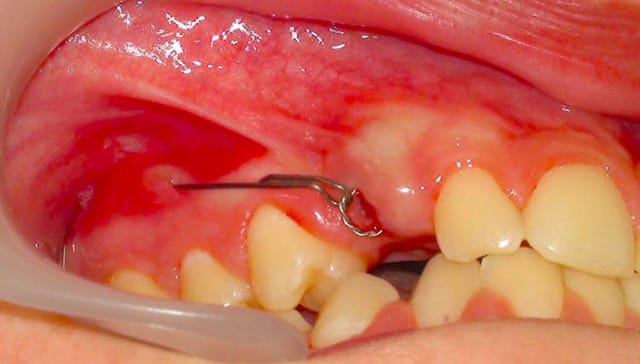

La suite : on a dégagé et collé un bouton sur sa couronne en même temps qu'on a viré la 53..

Et maintenant, qu'est-ce qu'on fait ?

Il nous faut des points d'appui pour la tracter en vestibulaire !